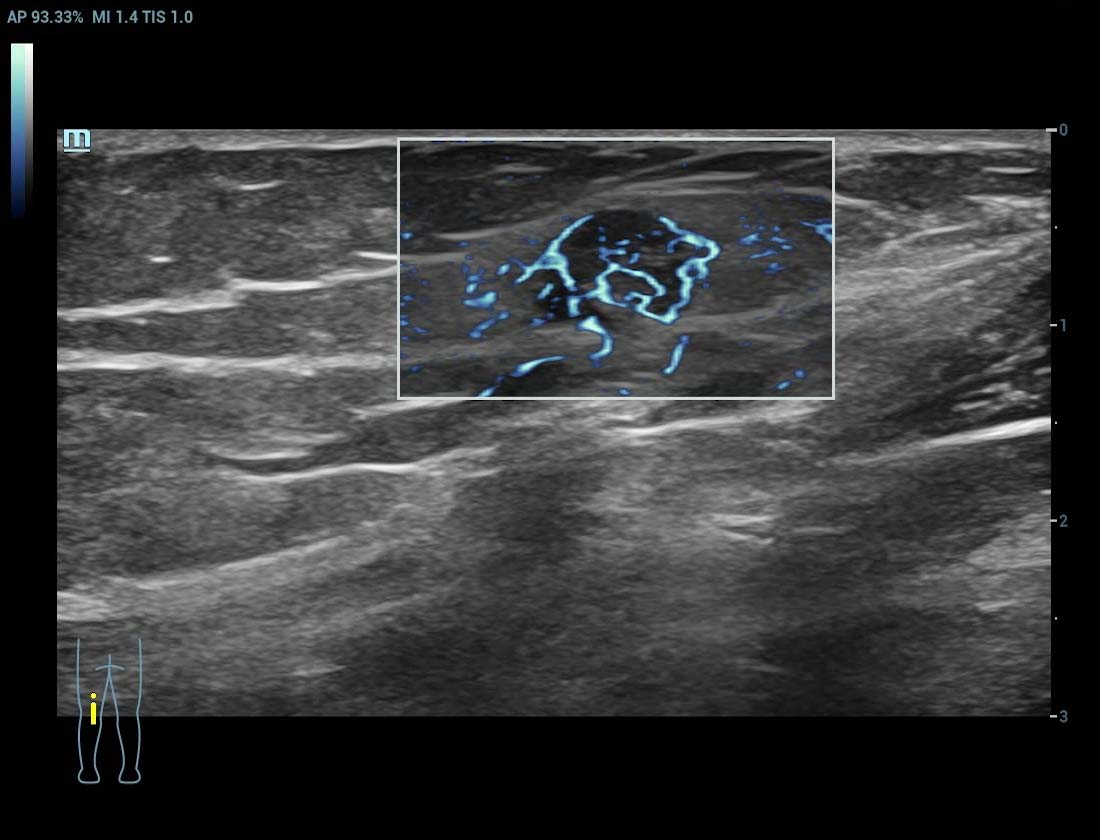

Angiografia ultramicroscû°pica (Ultra Micro Angiography, UMA)

UMA aumenta a confian?a diagnû°stica ao expandir a visibilidade dos fluxos sanguûÙneos atûˋ o nûÙvel de vasos minû¤sculos, com sensibilidade e resolu??o superiores.

sUMA ã Rins

sUMA ã C?ncer de tireoide

sUMA ã Nû°dulos linfûÀticos

sUMA ã Les?o em MSK